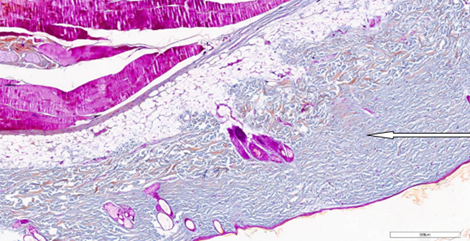

Морфологическое исследование образцов. Результаты микроскопического исследования биоматериала, полученного у экспериментальных животных на 14-й день, свидетельствовали о наличии более выраженных морфологических изменений в группе1. Помимо истончения эпидермиса у одной особи (№3), лазерное воздействие способствовало изменениям стратификации сетчатого слоя дермы (особь №2; рис.3) и коллагеновых волокон (особь №3). При этом изменения в дерме у животных из группы2 были выражены в меньшей степени, за исключением ангиоматоза у крысы №3, который сопровождался воспалительной реакцией в поверхностном слое дермы (рис. 4).

Рис. 4. Скудная воспалительная инфильтрация в поверхностном слое дермы на 14-й день после процедуры воздействия RF-микроиглами. Окрашивание гематоксилином и эозином (х400). Примечание: рисунок составлен авторами по результатам данного исследования